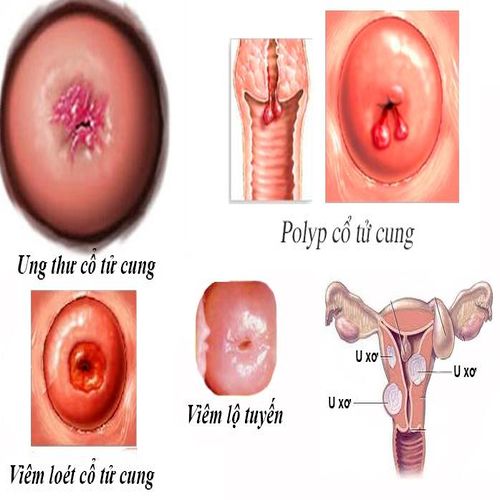

Viêm cổ tử cung là tình trạng viêm nhiễm, phù nề và sưng mủ lở loét tại vùng cổ tử cung do tác động trực tiếp từ vi khuẩn gây hại, nấm men, ký sinh trùng hay virus. Bệnh có thể gây đau đớn nhiều cho chị em, đặc biệt ở vùng hạ vị, rối loạn chu kỳ kinh nguyệt và chức năng vốn có của cổ tử cung.

- Viêm cổ tử cung mãn tính: Vùng cổ tử cung bị viêm nhiễm kéo dài ở giai đoạn cấp tính và không được điều trị hợp lý. Những triệu chứng ở giai đoạn này thường diễn ra khá âm thầm nhưng có tác động mạnh mẽ đến sức khỏe, có nguy cơ biến chứng về sau.

Ngoài ra, chị em đang mắc các bệnh lý phụ khoa như viêm âm đạo, viêm âm hộ, viêm lộ tuyến cổ tử cung, viêm nhiễm vùng chậu thì nguy cơ dẫn đến bệnh lý cổ tử cung là rất cao. Do đó, ngay khi nhận định vùng kín có những dấu hiệu bất thường, chị em nên khám và điều trị càng sớm càng tốt để bảo vệ sức khỏe.

- Gia tăng nguy cơ mắc bệnh phụ khoa: Vi khuẩn phát triển tại cổ tử cung sẽ dễ dàng xâm nhập đến các vùng khác, từ đó chị em xuất hiện nguy cơ cao mắc các bệnh lý về phụ khoa như: viêm phần phụ, viêm nội mạc tử cung, viêm lộ tuyến cổ tử cung,… ảnh hưởng nghiêm trọng đến sức khỏe, tâm lý.

- Có khả năng biến chứng thành ung thư cổ tử cung: Thống kê cho thấy, những người mắc viêm cổ tử cung thường có nguy cơ bị ung thư cổ tử cung cao hơn so với người khác. Các chuyên gia cho rằng, việc viêm cổ tử cung tái phát nhiều lần làm phát sinh các tế bào ung thư cổ tử cung.